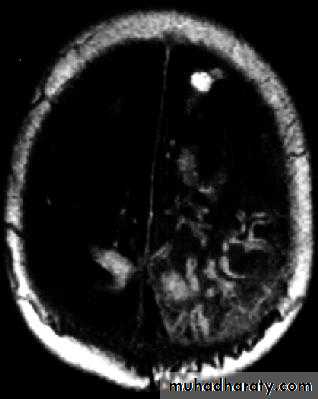

Multilocular Abscess

د.عبدالرحمن

• Multilocular abscess.